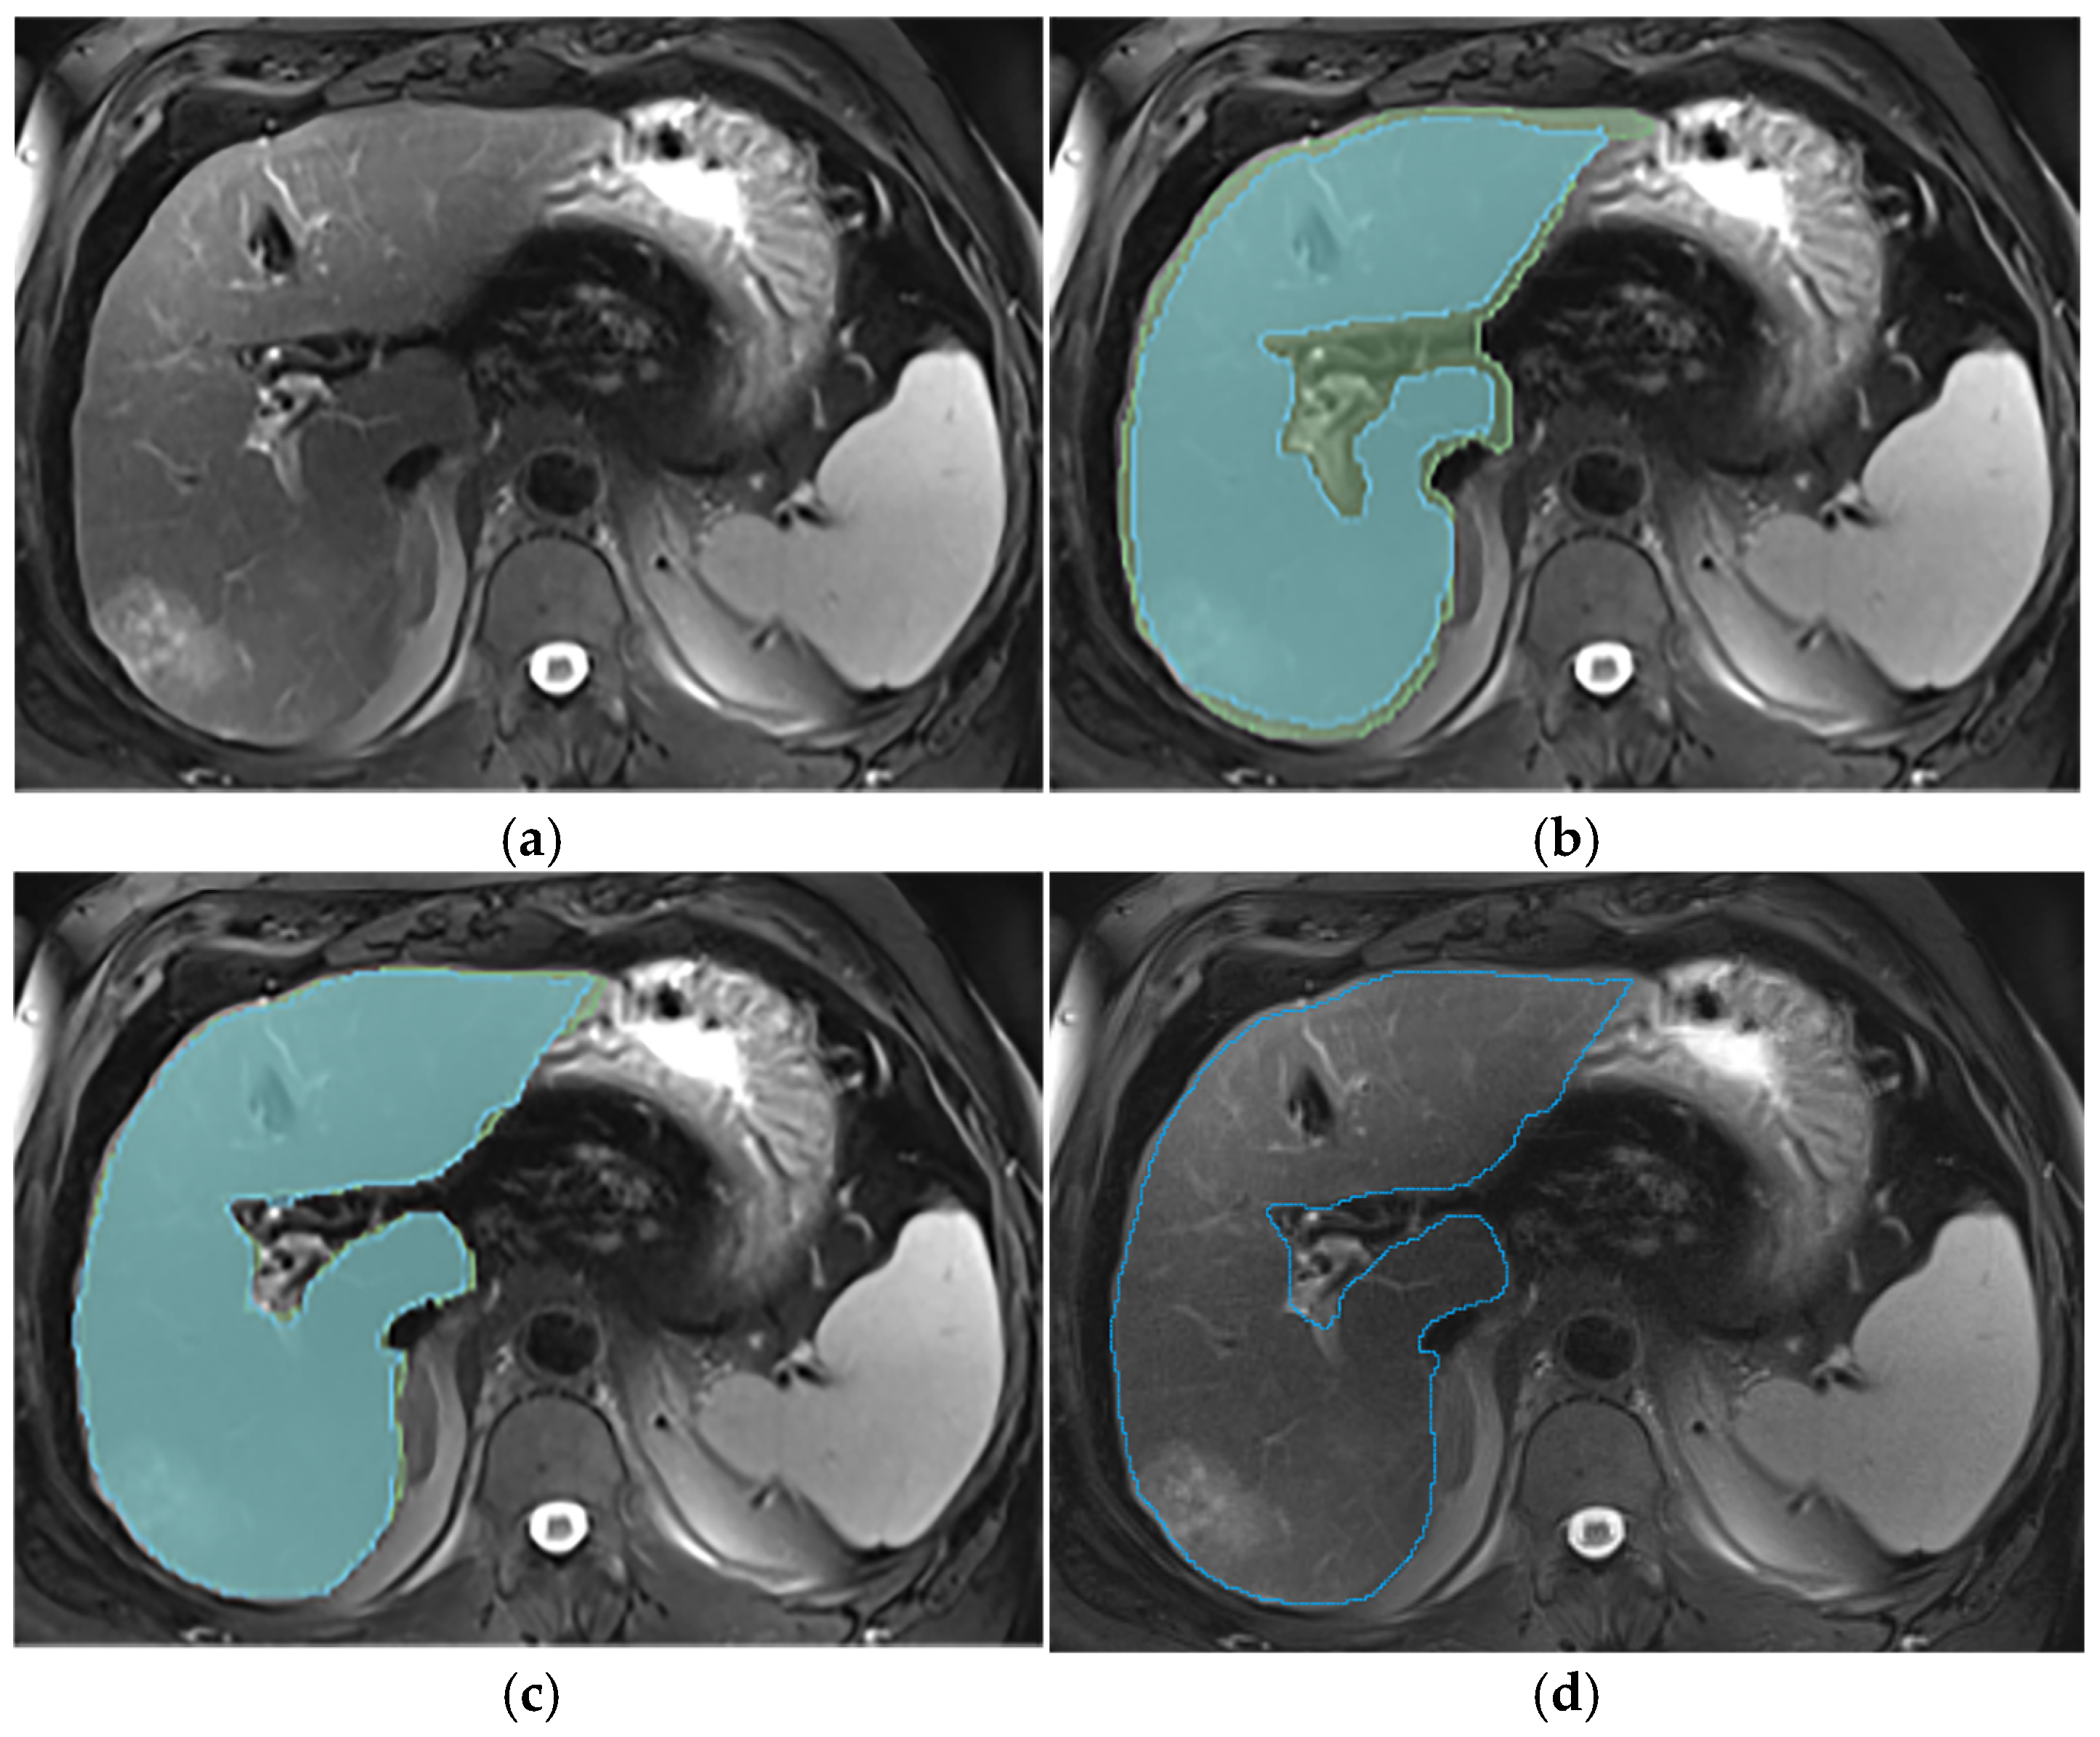

Appendix A.2. Hepatic Hilum Segmentation

Appendix A.3. Vascular Segmentation

Appendix A.4. Ligaments Segmentation

Appendix A.5. Multi-Part Liver Parenchyma